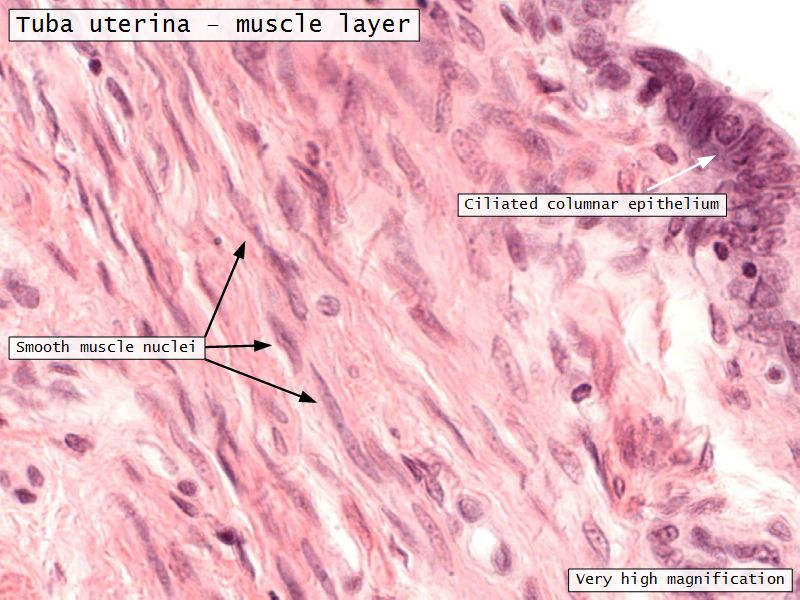

Tuba uterina

Tuba uterina

- Muscular tube

- Most frequent site of fertilization

- Conveys zygote to uterus

- Four regions

- Three layers

Three layers

- Mucosa

- Muscular layer

- Serosa

Mucosa

- Epithelium

- Lamina propria

Epithelium

- Simple columnar

- 2 types of cells

- Peg cells

- Secretory cell

- Ciliated cells

- Beats towards uterus

- Facilitate movement of zygote to uterus

Muscular layer

- Ill-defined

- Inner circular

- Outer longitudinal

- Play role in moving zygote towards uterus